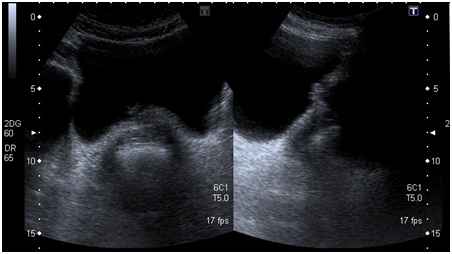

A 54-year old white woman, without significant past medical history other than menopause since 2years ago presented with post coital hematuria and also she had urinary tract infections (UTIs), documented by urine cultures (Proteus Mirabillis). No other associated symptoms. She received antibiotic therapy with quinolones. The urine cytology was negative. The assessment by the Gynecology service was normal. The renal ultrasound (US) Each kidney was normal, preserved cortico medullary differentiation and without dilated collecting systems. There was irregularity zone in the mucosa close to bladder neck, measuring 1x0.5cm. Cystoscopy revealed an edematous and erythematosus lesion of 1x1.5cm in the posterior wall of the bladder neck that extended into the urethra. In pelvic magnetic resonance imaging (MRI) a pelvic mass was evident measuring 35x38x47mm, widening the bladder neck at this level, nonspecific inguinal adenopathies and a left iliac node with malignancy aspect.

Initial US

The pelvic examination during the transurethral resection of bladder (TURB) revealed a palpable nodule on the anterior wall of the vagina and there was not others remarkable findings. The pathology of transurethral resection of bladder confirmed urethra adenocarcinoma muscle-invasive with invasion of bladder neck. She was taken to an extension study (toracoabdominopelvic scan) in which the metastatic lesions were discarded (Figure 1-3).

Figure 1 Initial pelvic ultrasound.

Figure 2 Initial pelvic ultrasound.